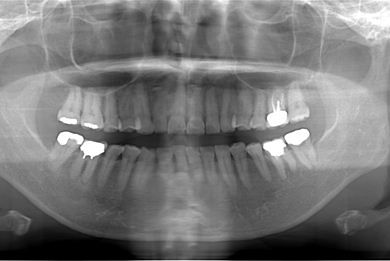

| 性別/年齢 | 女性 / 31歳 | ||||||||||||||||||||||||||||||||

| 主訴 | 前歯の歯茎が黒ずんでいるので、改善したい。 | ||||||||||||||||||||||||||||||||

| 治療方針 | 上顎前歯、メタルボンドセラミッククラウンからオールセラミッククラウンにする事で、審美的回復を行う。 | ||||||||||||||||||||||||||||||||

| 治療内容 | CAD/CAMオールセラミッククラウン2本(セラミック用土台2本) | ||||||||||||||||||||||||||||||||

| 総治療費 | 142,800円 | ||||||||||||||||||||||||||||||||

| 治療期間 | 2ヶ月 |